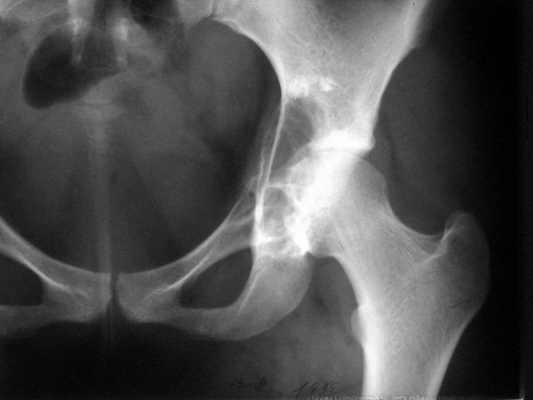

Женщина 22 лет поступила с протрузией вертлужной впадины.Рентгенограммы (1, 2) с интервалом в 1 год. В онкодиспансере сделали биопсию - ОБК без малигнизации. Какой объем операции здесь следует предпринять? Есть ли какие-то шансы на первичное эндопротезирование? Где такие операции делают? В том числе в Европе. Заранее спасибо.

The xray appearance is consistent with a bengin aggessive or malignant lesion involving both the acetablum and the femoral epiphysis (there appears to be erosions of the femoral head). The differential diagnosis would include non-tumor conditions such as Brown's tumor (a serum calcium should be measured), benign aggressive lesions such as GCT, ABC and chondroblastoma, and malignant lesions such as telangiectatic osteosarcoma and MFH of bone.

However, the extent of the tumor in the pelvis and lack of a cortical rim leading to a large uncontained defect would be too much bone loss for any type of acetabular reconstruction.

A wide resection with reconstruction with a saddle modular prosthesis would be an option depending on the status of the remainder of the ilium.

looking to the X-rays and CT scan it appears this young lady has an aggressive bone leasion.

The X-ray and CT scan appearance is likely as the chondrosarcoma what is seldom but common

finding in the replacement surgery of the hip. Having precise histological, CT and MRI data should be planed the amount of surgery after detailed discussion with patient. There is no any possibility to perform primary replacement. If there is the chondrosarcoma hemipelvectomy would be the most live saving procedure. If there is an aggressive giant cell tumor or other findings about allografting, reconstructive surgery with custom made implant or saddle modular prostheses (W.Link) could be discussed. In other wards there are so many different thinks what should be discussed with patient